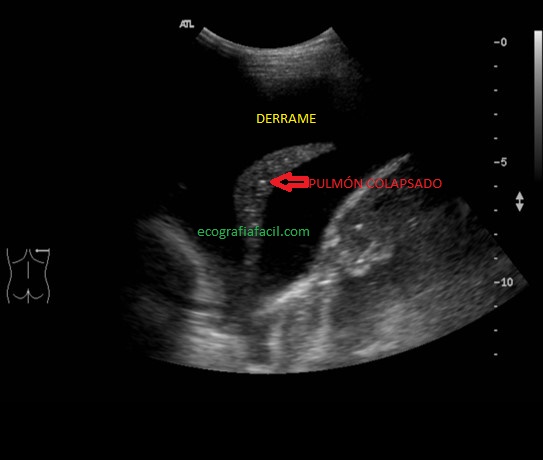

En otras ocasiones podemos ver pulmón colapsado y «flotando» literalmente en la cámara líquida, como señala la flecha roja de la imagen superior.

At other times we can see lung collapsed and «floating» literally in the liquid chamber, as indicated by the red arrow in the image above.